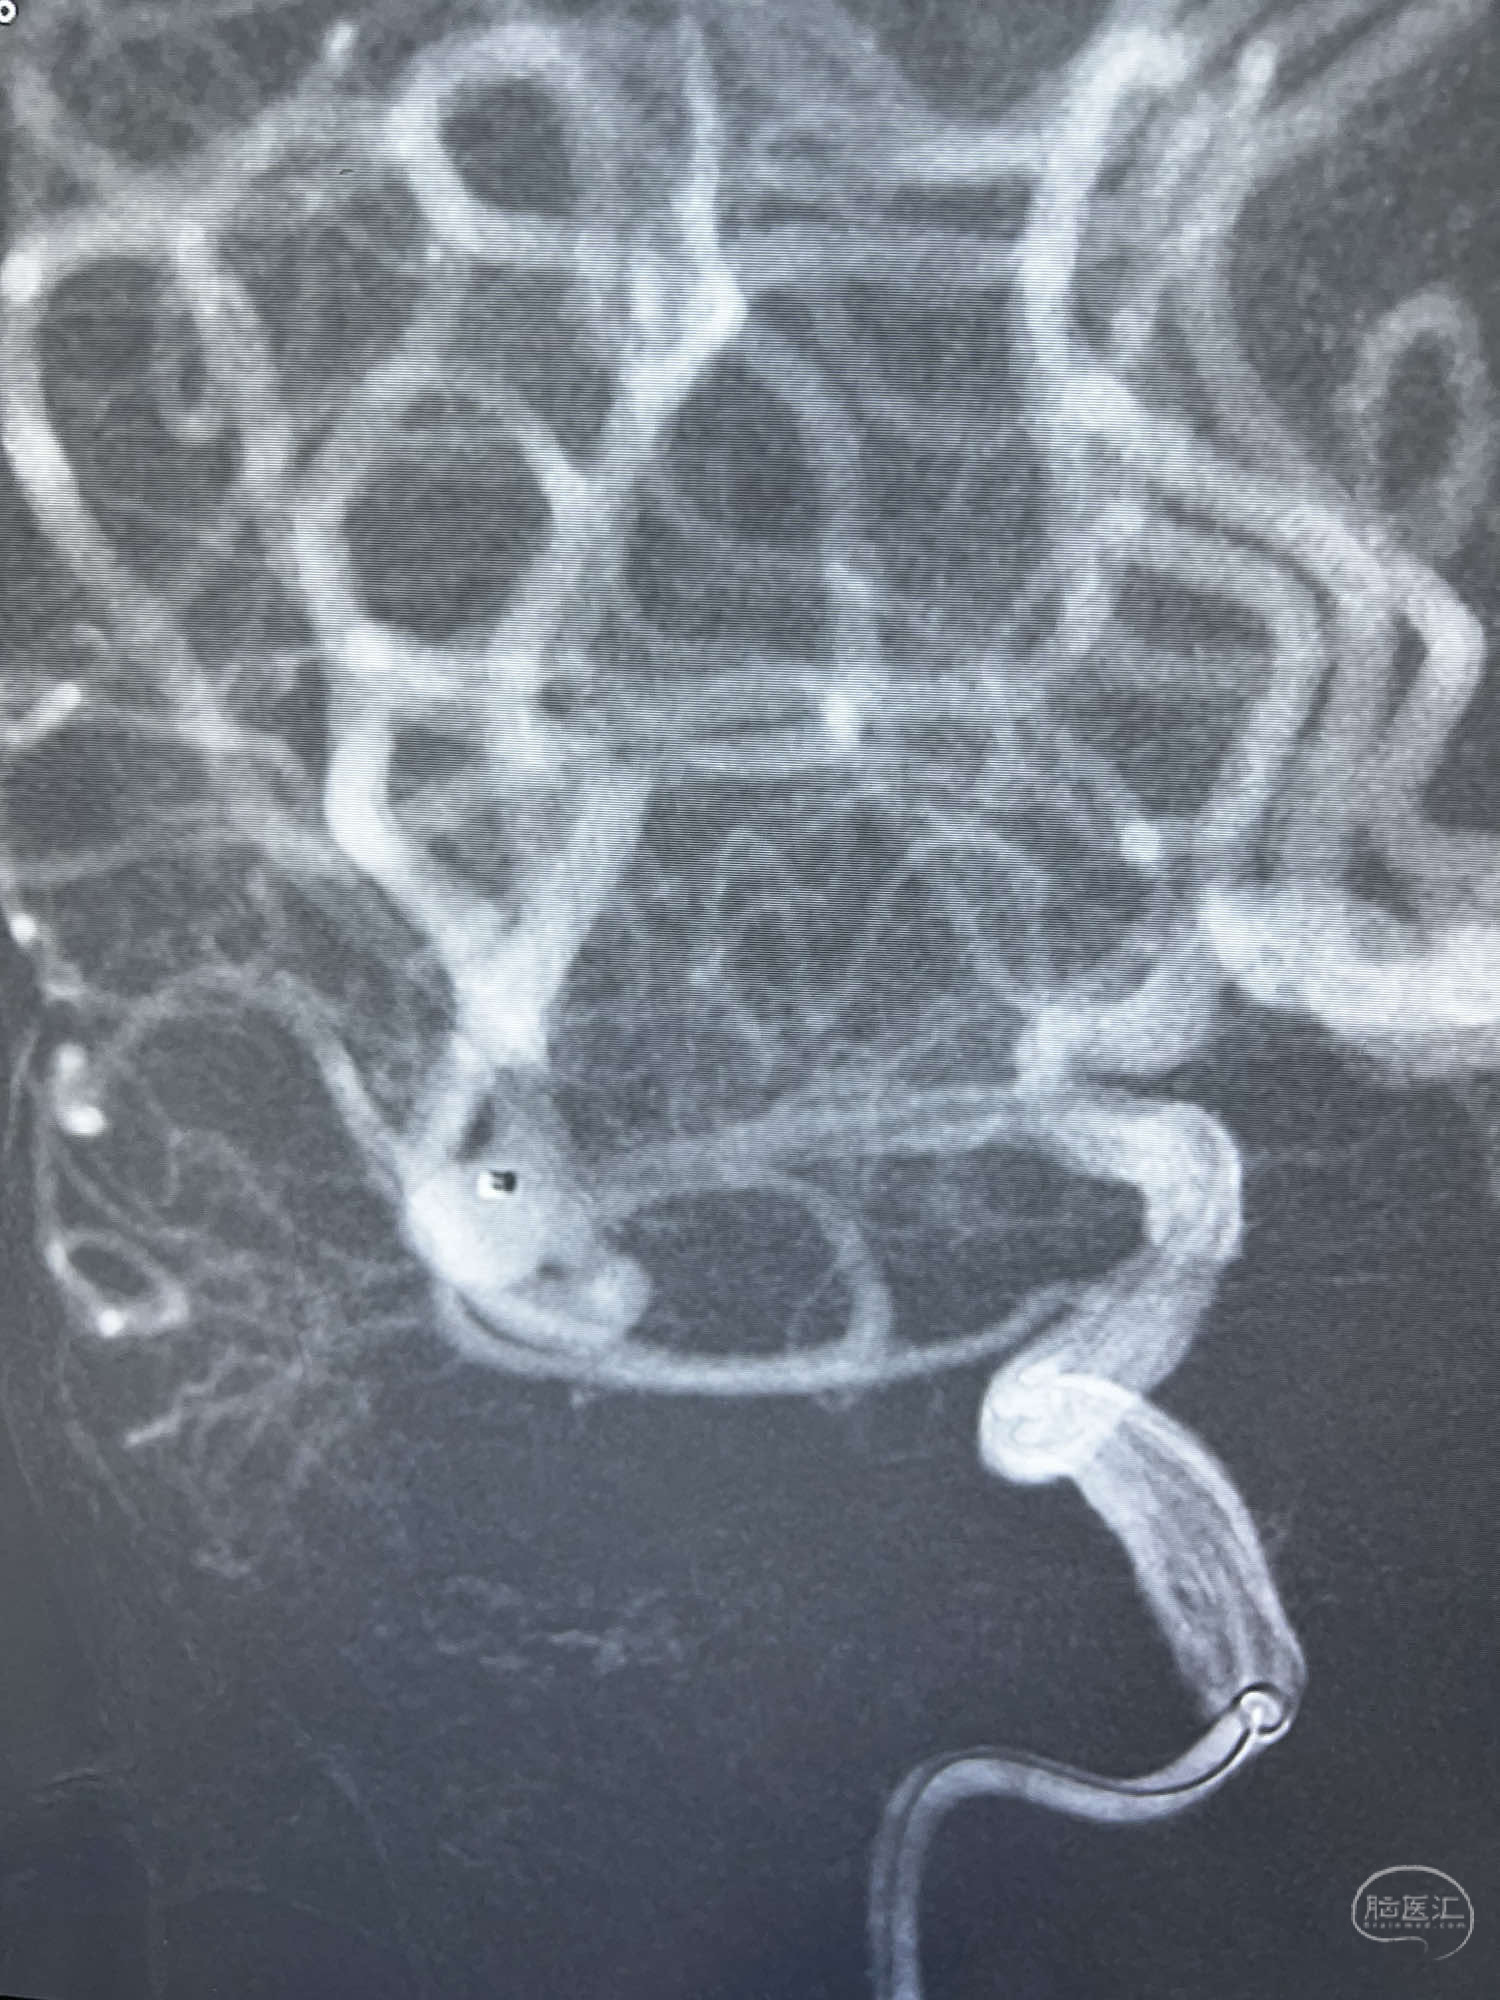

6F Neuromax➕6F115cm 心玮中间导管建立路径,sychro14微导丝➕VIA21超选至动脉瘤体内近中部,WEB5mmx3mm植入动脉瘤。

WEB瘤内扰流装置5mmx3mm经过“种子、萌芽、开花”三个阶段,打开后良好贴壁,动脉瘤内血液滞留,载瘤动脉通畅。WEB一步到位,通过瘤内扰流的方式起到栓塞动脉瘤的作用,避免了应用支架保护分支血管,简化了操作步骤,降低了术中血栓及出血的风险。